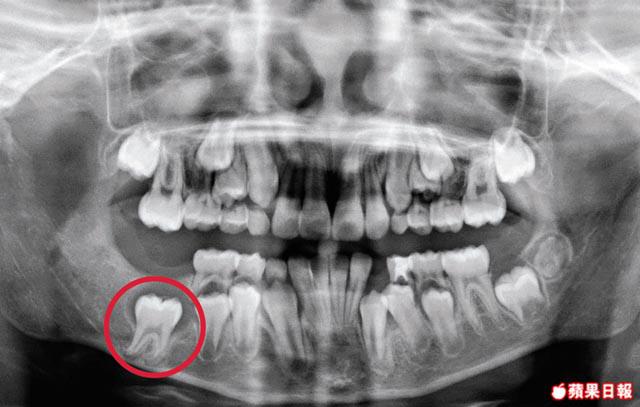

【本報訊】智慧齒不長出來,原來隨時是長了良性腫瘤的警號,曾有患者因大牙鬆開求診,發現右下顎智慧齒長了一個五厘米的囊腫,最終要脫掉三隻牙。有口腔頜面外科醫生指,腫瘤可侵蝕牙齒及面骨,延誤治療會增加骨折風險。

今年42歲的張女士,因右下顎有兩顆大牙「鬆鬆哋」求診,檢查後發現一直沒有長出來的右下顎智慧齒,有一個約五厘米的腫瘤,更侵蝕附近兩顆大牙的牙腳,導致鬆脫,需全身麻醉除去智慧齒、腫瘤及附近兩顆大牙。

荃灣港安醫院口腔頜面外科專科醫生謝杰明指,成長中的恒齒均有水囊包圍,與口腔黏膜連接後,牙齒便會長出,但若牙齒不能長出,水囊可演變成囊腫,屬一種良性腫瘤,約四成牙齒良性腫瘤與下顎智慧齒有關。他稱,由於腫瘤生長緩慢,不會引起任何症狀,往往不易察覺,多是接受牙科檢查時發現。

牙齒的良性腫瘤不會演變成惡性,但謝杰明指,囊腫會積水並向四周生長,侵蝕牙齒及面骨,令骨骼變得脆弱,一旦遇到撞擊,或會出現嚴重骨折;即使智慧齒已長出,若有水囊組織殘留,也可引致腫瘤。他指,曾有一名43歲女病人因右臉腫脹求醫,檢查後發現右下顎已長出的智慧齒下,連着一個約兩厘米的腫瘤,需以手術切除。